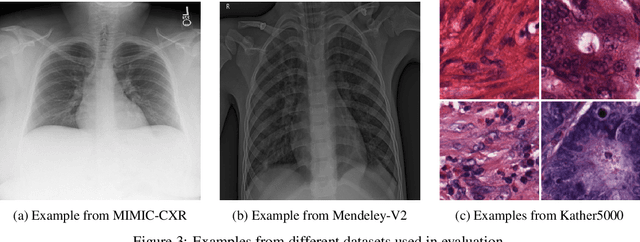

When training deep neural networks for medical image classification, obtaining a sufficient number of manually annotated images is often a significant challenge. We propose to use textual findings, which are routinely written by clinicians during manual image analysis, to help overcome this problem. The key idea is to use a contrastive loss to train image and text feature extractors to recognize if a given image-finding pair is a true match. The learned image feature extractor is then fine-tuned, in a transfer learning setting, for a supervised classification task. This approach makes it possible to train using large datasets because pairs of images and textual findings are widely available in medical records. We evaluate our method on three datasets and find consistent performance improvements. The biggest gains are realized when fewer manually labeled examples are available. In some cases, our method achieves the same performance as the baseline even when using 70\%--98\% fewer labeled examples.